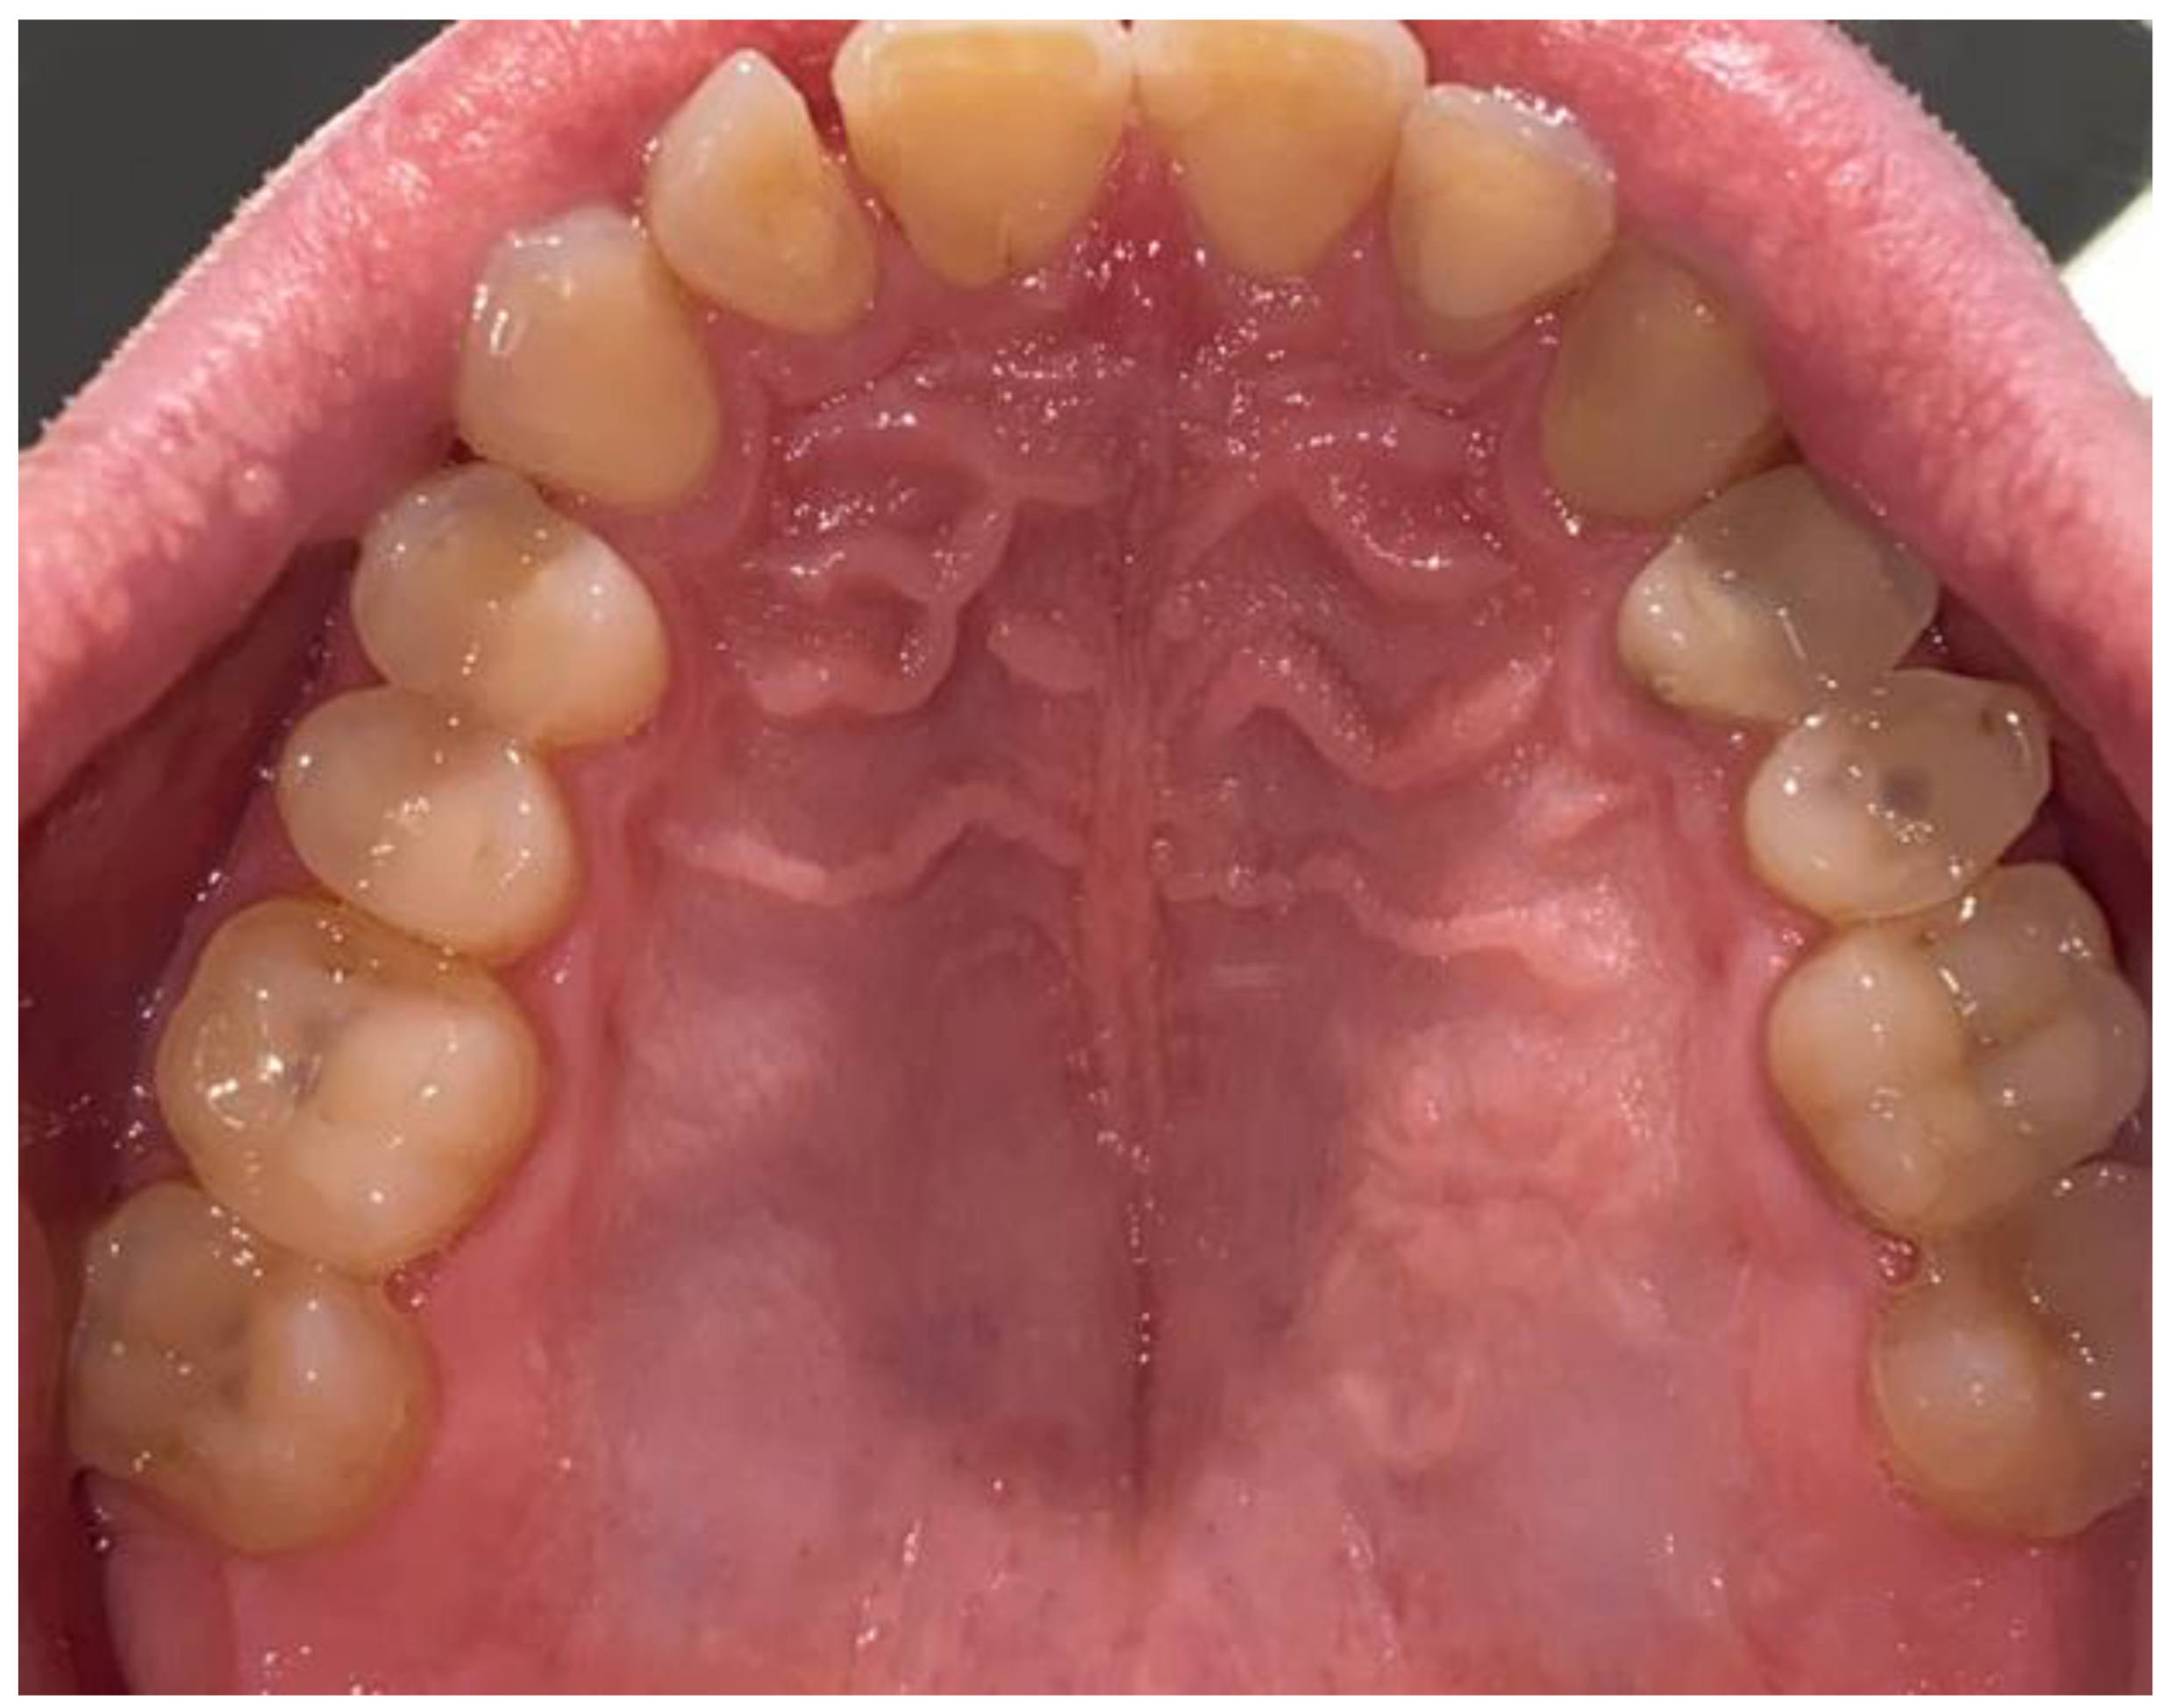

2. Case Description